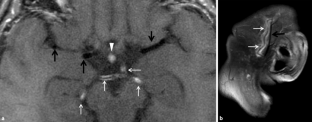

Abb. 2